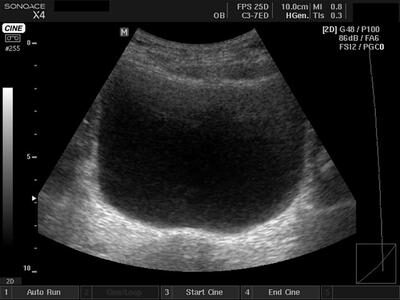

Диагностирование ультразвуком предстательной железы может производиться двумя способами:

• Траснабдоминальным, проводимым посредством брюшной стенки. Этот метод не имеет противопоказаний к применению. Однако, если на брюшной области имеется большая рана или находится дренажная трубка, то выполнение УЗИ затрудняется. Чтобы улучшить визуализацию простаты, врач рекомендует наполнить мочевой пузырь. Причем наполнение мочевого пузыря должно быть средним. Так как не только не дополненный, но и переполненный орган может ухудшить обзор предстательной железы.

• Трансректальный метод производится посредством введения ультразвукового датчика через анальное отверстие на 5 см в прямую кишку. При помощи данного способа, благодаря близкому расположению простаты, можно получить наиболее точную оценку органа. Кроме того, если возникнет необходимость, то можно взять анализ ткани на биопсию. Чтобы провести трансректальное УЗИ, не требуется предварительно наполнять мочевой пузырь.

Точно узнать объем простаты позволяет метод трансректальной ультразвуковой диагностики (ТРУЗИ). Во время обследования специальный датчик вводится через просвет прямой кишки непосредственно в изучаемую область. С целью получения более точных результатов врачам рекомендуется самостоятельно осуществлять расчет объема органа на основе полученных линейных размеров железы. Помимо ТРУЗИ, для определения величины простаты в урологии применяются следующие методы:

3. Трансабдоминальное УЗИ (ТАУЗИ) – предусматривает обследование органа через стенку брюшины. ТАУЗИ помогает оценить массу, объем, контуры предстательной железы.

Какой шириной, длиной, толщиной обладает простата, позволит наиболее точно определить метод трансректальной ультразвуковой диагностики (ТРУЗИ). Датчик вводят через просвет прямой кишки в область простаты. Основным преимуществом методики является то, что проводить обследование можно без необходимости заполнения мочевого пузыря.

Объем органа при использовании диагностического метода трансректального УЗИ имеет более достоверные показатели, если доктором, который проводил обследование, будет выполнена расшифровка результатов самостоятельно, которые основаны на выявленных линейных размерах железы. Несмотря на применение современного диагностического медицинского оборудования, результаты автоматических подсчетов могут быть незначительно искажены, особенно при наличии узловых формирований в тканях простаты.

3. Трансабдоминальное УЗИ предстательной железы (ТАУЗИ). Диагностический метод подразумевает проведение наружного обследования через стенку брюшины. Наиболее простой, доступный метод диагностики в урологии, применяемый во многих медицинских центрах. Сканирование проводят в поперечном и продольном направлениях. Данная методика диагностики позволяет оценить, какой размер имеет простата, а также определить массу, объем, контуры органа. Проведение ТАУЗИ затруднено, если человек имеет большой вес, страдает ожирением.